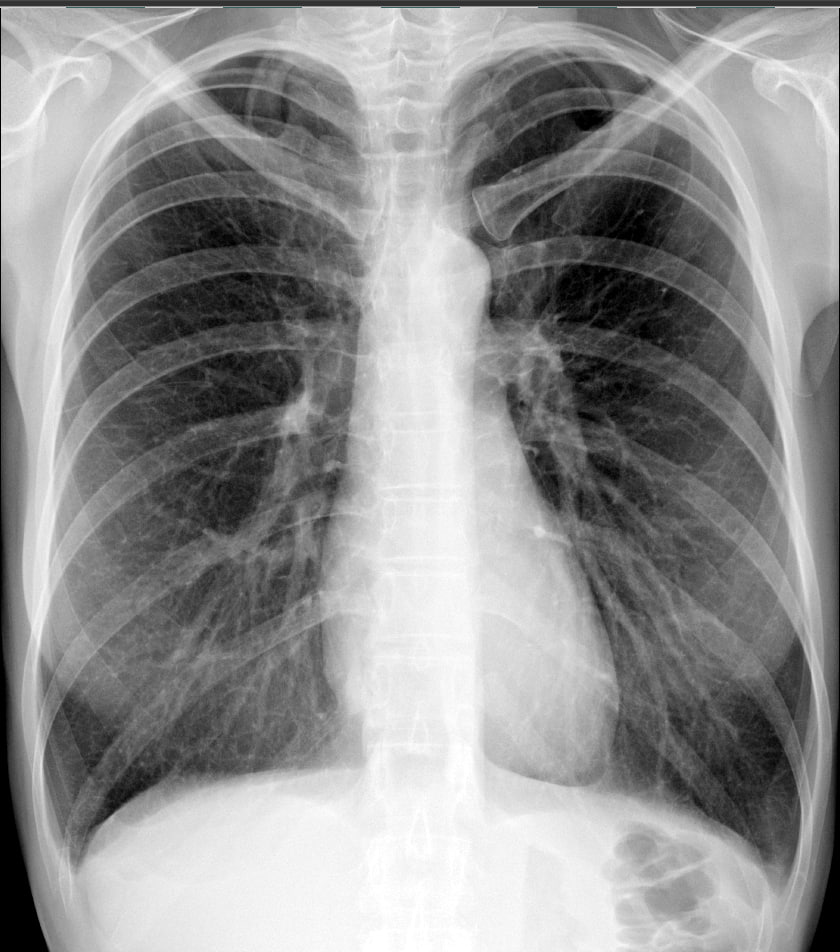

1. склероз или аневризма? (при этом год назад было все в порядке)

Не нахожу ни склероза( вероятно Вас интересовал пневмофиброз),  ни аневризмы( не уточненной чего), ни релаксации одного из куполов диафрагмы. Легкие и сердце в пределах нормы.

Мне как раз в описании написали: склерозирована дуга аорты, диафрагма частично релаксированна (на словах объяснили тем, что внизу контур не гладкий и есть какие то спайки). Посмотрела снимок годичной давности, там действительно был гладкий четкий контур диафрагмы. Про пневмофиброз в описании и в заключении нет ничего. Поэтому обратилась за сторонним мнением. Если все в пределах нормы, то получается склерозированной дуги аорты нет? И по снимку нет пневмофиброза? Тогда не понятно что искать, симптоматика у меня не очень, отдышка также присутствует.

По существу мне не чего добавить к вышеизложенному( норма). Да, Вам и рентгенолог ничего плохого не написал, тоже норму. По мелочам, не имеющим ни какого значения сложно говорить и противоречить "Диафрагма расположена обычно, частично релаксирована" ( при том, что она имеет два купола, правый и левый). Не факт, что " ... дуга аорты склерозирована", а не скиалогия связанная с задним отрезком ребра и позвоночником. Ваша симптоматика ни как не связана с рентгенограммой гр. клетки и лучше всего обратиться к неврологу.